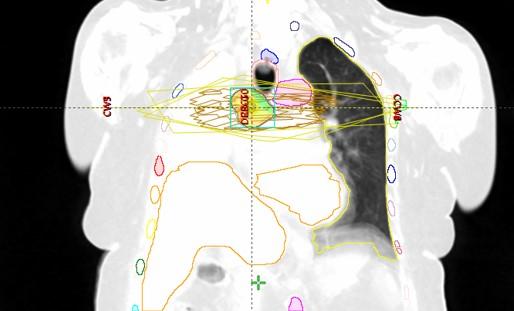

Bolesnica, rođena 1958. Dijagnoza: Adenocarcinoma lobi inferioris pulmonis sinistri